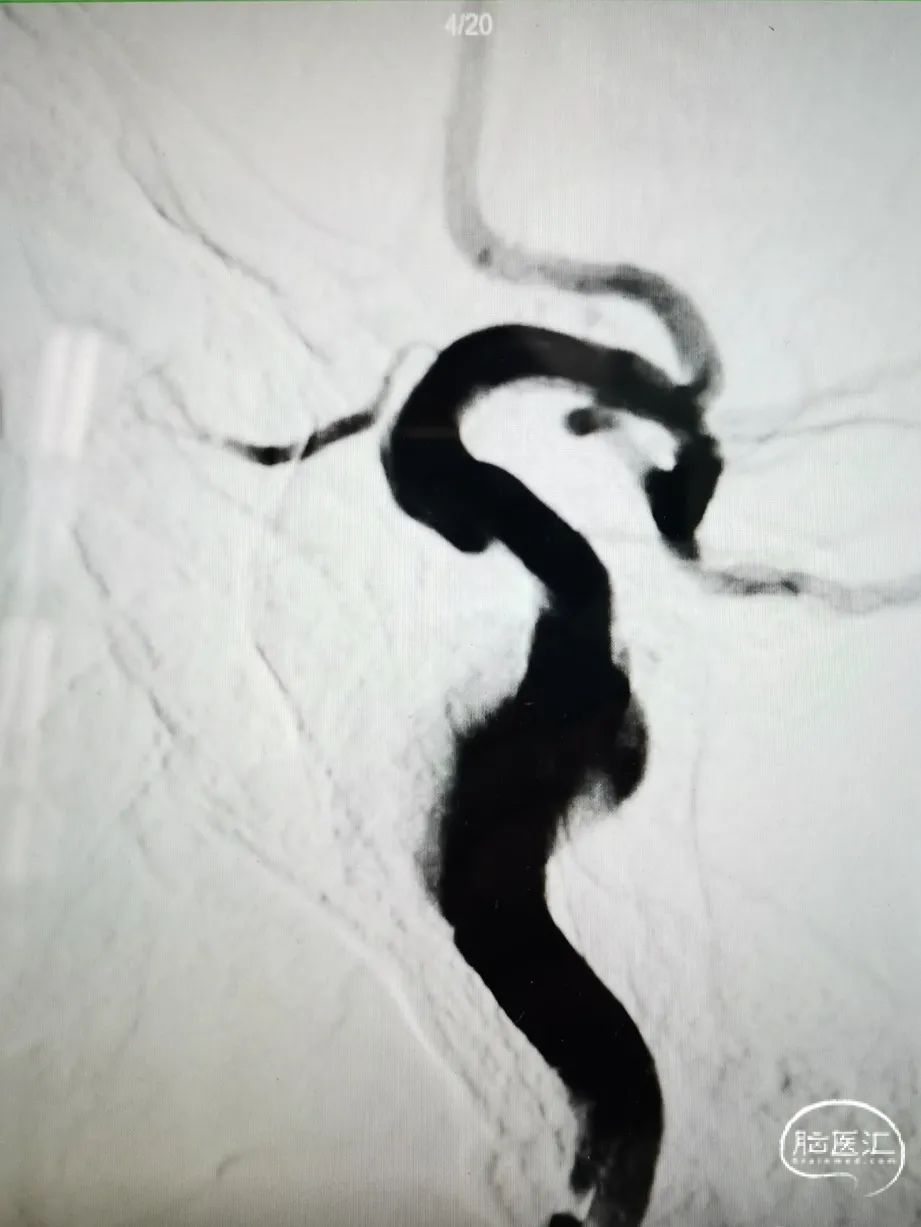

DSA造影

造影提示主动脉弓开口尚可,但颈动脉迂曲明显。

前交通囊状动脉瘤约4mm╳3mm,瘤颈约4mm。

右颈内动脉交通段以远瘤样扩张,载瘤动脉完全瘤化,局部可见多处小阜突起,无明显瘤颈,最大约16mm╳11mm。

右侧后交通动脉自瘤体远端发出。

右侧大脑中动脉直径约3mm,颈内动脉海绵窦段约4.5mm。

图4